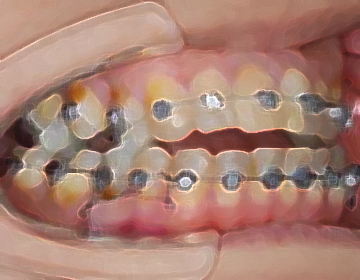

通常のワイヤーではできない移動はベンド(曲げる)したワイヤーでおこないます。

身体の反応を診ながら、噛み合わせ位置を微調整します。